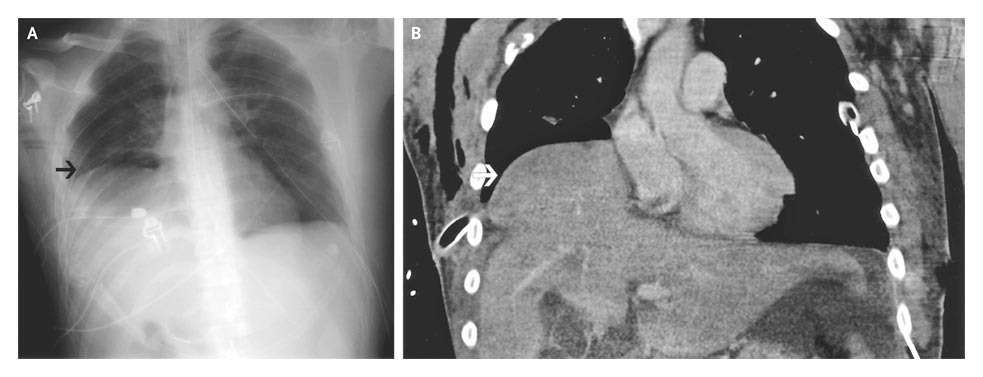

After resolution of the right hemopneumothorax, an elevated right hemidiaphragm was seen on a postoperative chest radiograph, a finding that suggested traumatic diaphragmatic rupture (Panel A, arrow).